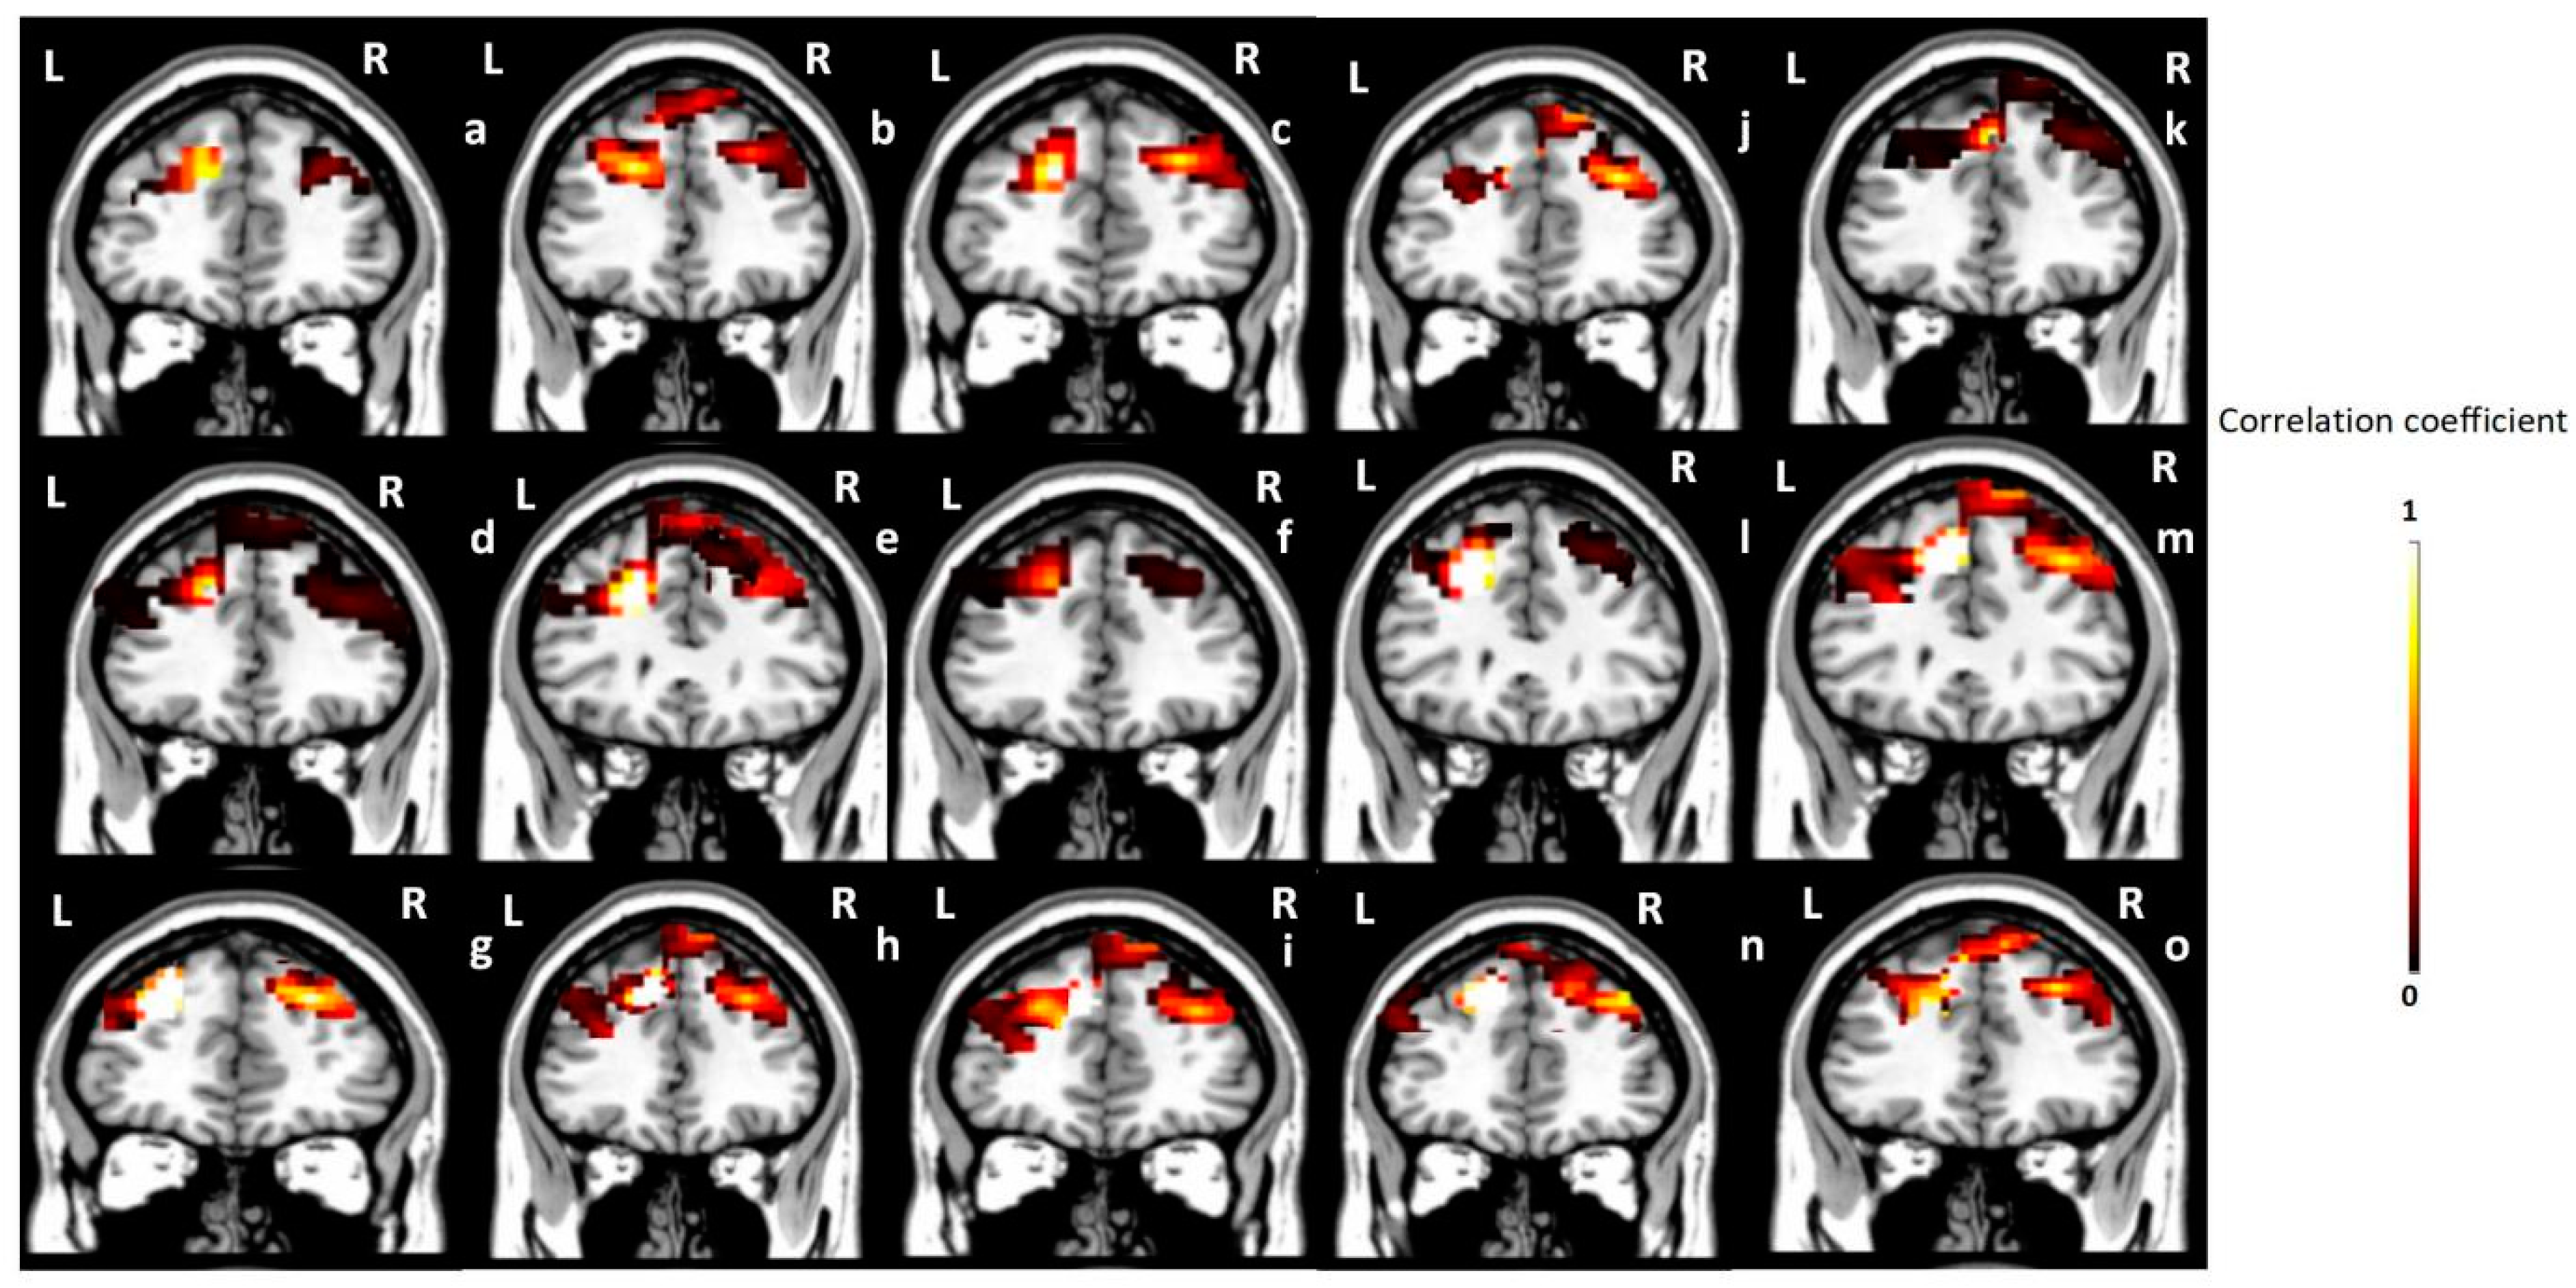

3.3. Seed-Based Correlation Analysis Results